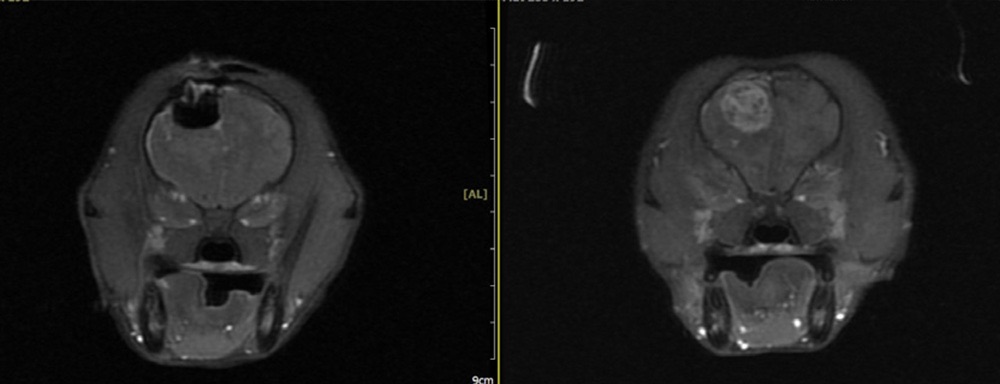

MRI 기반 정확 진단

반려동물의 뇌종양을 정확하게 평가하기 위해 사용되는 핵심 영상 진단 장비입니다.

MRI는 뇌 조직의 미세한 구조와 병변을 고해상도로 촬영할 수 있어, 종양의 위치·크기·경계는 물론 주변 신경 조직과의 관계까지 정밀하게 확인할 수 있습니다. CT나 X-ray로는 구분이 어려운 연부조직 변화까지 확인할 수 있어, 종양의 종류를 감별하고 수술 가능 여부접근 방향을 판단하는 데 중요한 기준이 됩니다.

뇌수술 전후 MRI 비교 이미지